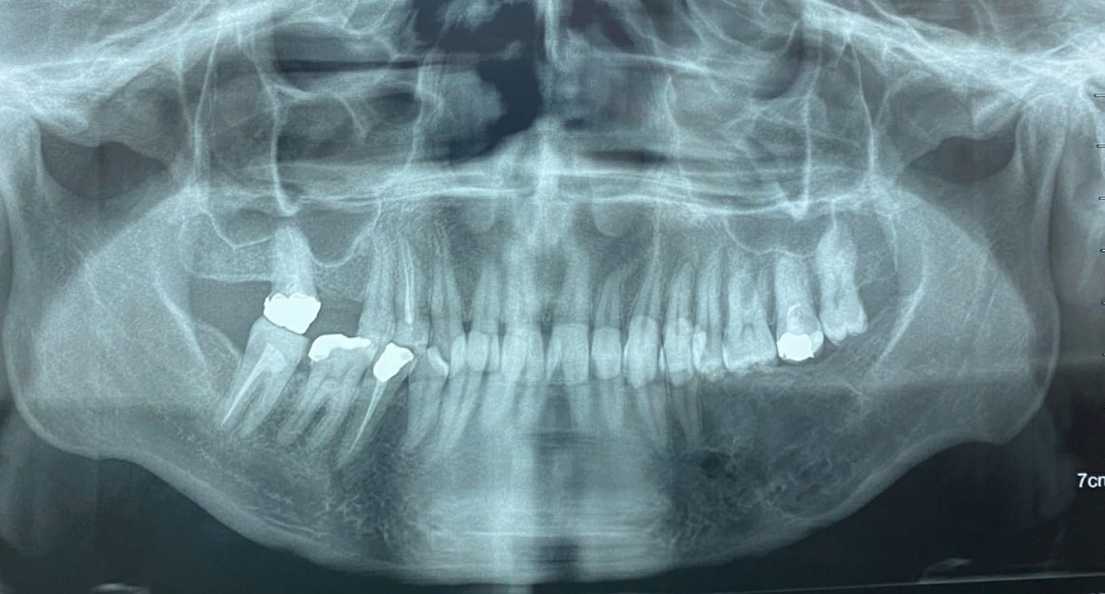

At 9 months follow-up, there was no sign of recurrence at both clinical and radiological examination. An orthopantomograph showed new bone formation in the resected zone. (Figure 7)

Figure 7. 9 months postoperative follow‐up OPT revealed a good amount of bone formation and no traces of recurrence.